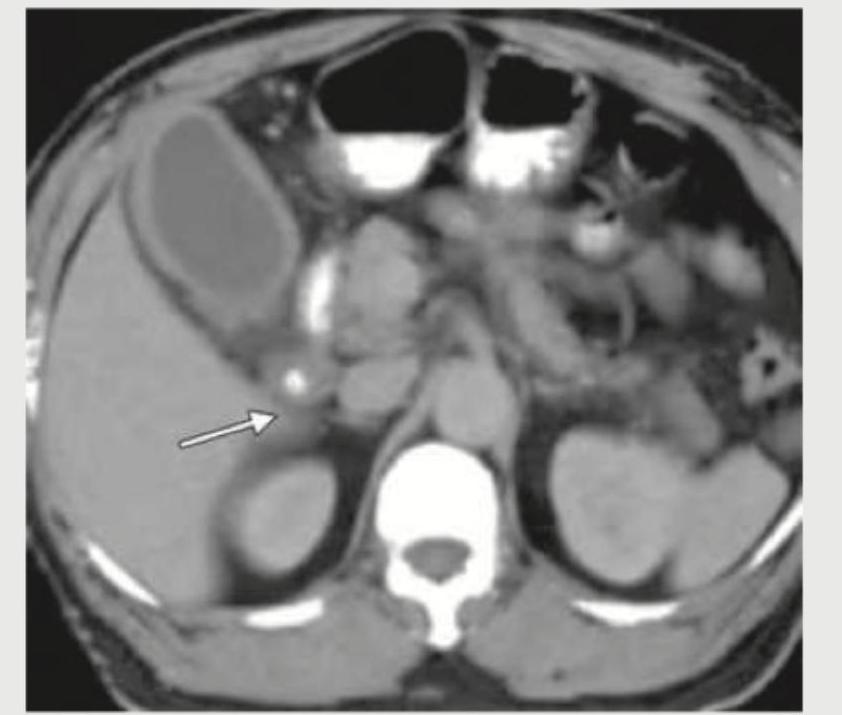

A 25-year-old patient underwent surgery for scoliosis correction. 5 days post-operatively he develops voluminous bilious vomiting. The given CT abdomen shows:

Explanation: ***SMA syndrome*** - The CT image shows significant **duodenal distention** proximal to the **superior mesenteric artery (SMA)**, characteristic of SMA syndrome. The arrow points to the **compressed third part of the duodenum** between the SMA and the aorta. - This condition is often seen post-scoliosis correction surgery due to rapid **spinal extension**, which can decrease the **aortomesenteric angle** and compress the duodenum, leading to **bilious vomiting**. *Paralytic ileus* - While ileus can cause vomiting and bowel distension, it typically involves **diffuse gaseous distension** of both small and large bowels without a discrete point of obstruction like the compressed duodenum seen here. - The clinical presentation of paralytic ileus post-operatively is more often characterized by generalized **absent bowel sounds** and abdominal distension, rather than specific bilious vomiting from high obstruction. *Pneumoperitoneum* - This refers to the presence of **free air in the abdominal cavity**, usually indicating a **visceral perforation**. - The provided CT image does not show any evidence of free air, and the presenting symptom of bilious vomiting is more indicative of obstruction. *Paravertebral abscess* - A paravertebral abscess would appear as a **fluid collection adjacent to the spine**, which is not depicted on this CT scan. - Clinical symptoms would likely include **fever, severe localized back pain**, and possibly neurological deficits, differing from the purely obstructive symptoms described.